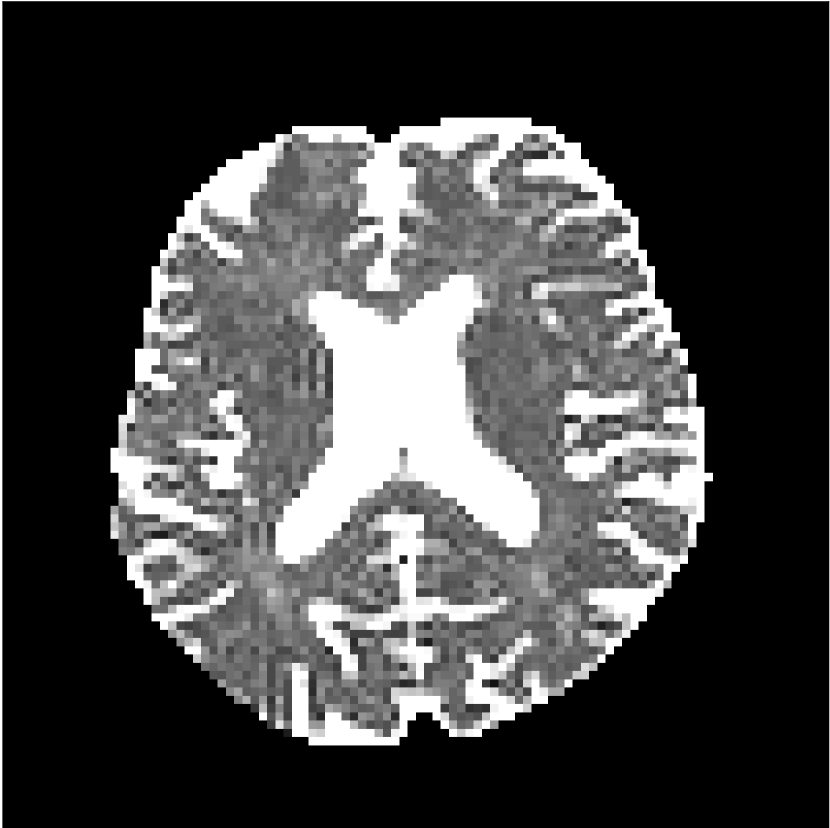

Figure 9 shows parameter maps for the different methods without partial Fourier (No PF) and with 5/8ths partial Fourier (5/8 PF). Mean diffusivities calculated from the raw DWI data (Raw) show notable noise and Gibbs ringing artifacts, while this is substantially removed with the state-of-the-art (SoA) method. However, the state-of-the-art method begins to lose its ability to compensate for the Gibbs ringing and resolution loss when partial Fourier is utilized in the acquisition. The effects of partial Fourier increases are primarily evident in the enlargement of the lateral ventricles and the presence of black lines in the vicinity of the lateral ventricles. The MCNN model is able to compensate somewhat for the ringing effects, but begins to introduce substantial artifacts at the 5/8ths partial Fourier factor, whereas the CCNN model continues to give high-quality mean parameter maps across all PF factors.

Raw

SoA

MCNN

Standard PF

CCNN

s/mm2

No PF

MD, m2/ms

5/8 PF

FA

MK

Similar trends are observed in the other diffusion parameter maps.